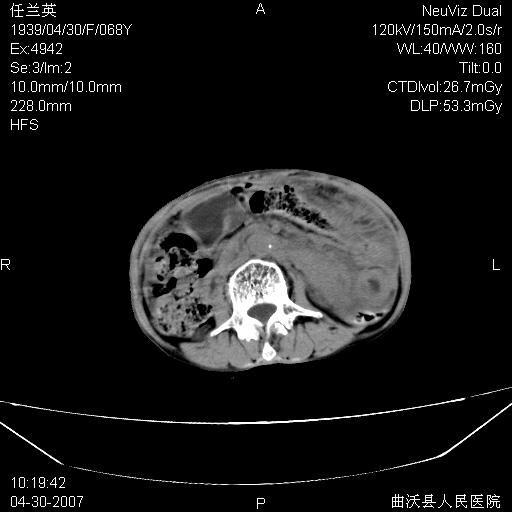

患者,女,68岁,感觉腹部憋涨发硬数天,查b超发现左盆腔有囊性肿物和少量腹水,行ct检查

1.考虑卵巢肿瘤并腹腔广泛性转移可能性大;

网膜、腹膜广泛转移考虑来源于左侧卵巢癌可能性大。不除外来源于消化系的肿瘤。

难,腹膜后淋巴结转移。

支持卵巢恶性肿瘤腹膜.肠系膜.淋巴结转移,

支持卵巢恶性肿瘤腹膜.肠系膜.腹膜后淋巴结转移,

难的一见 典型 - 网膜饼  冰冻骨盆 可以当教学片了